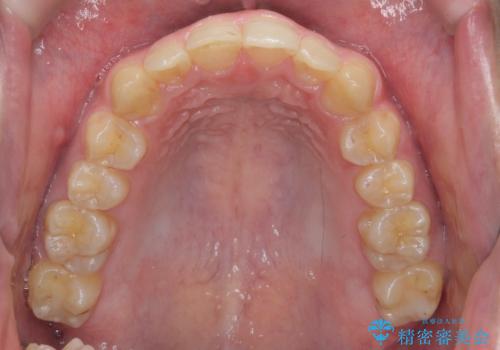

ガタつきの大きい前歯 インビザラインによるマウスピース矯正治療

- ガタつきの目立つ前歯の改善を求めて来院されました。

上顎前突、がたつきを改善すべく上顎臼歯の後方移動・ディスキングを行い歯並びの改善を計画します。

食事・歯ブラシ時以外の時間にしっかりとマウスピースを装着していただけたのでガタつきは大きく改善し良好な歯並びを得ることができました。